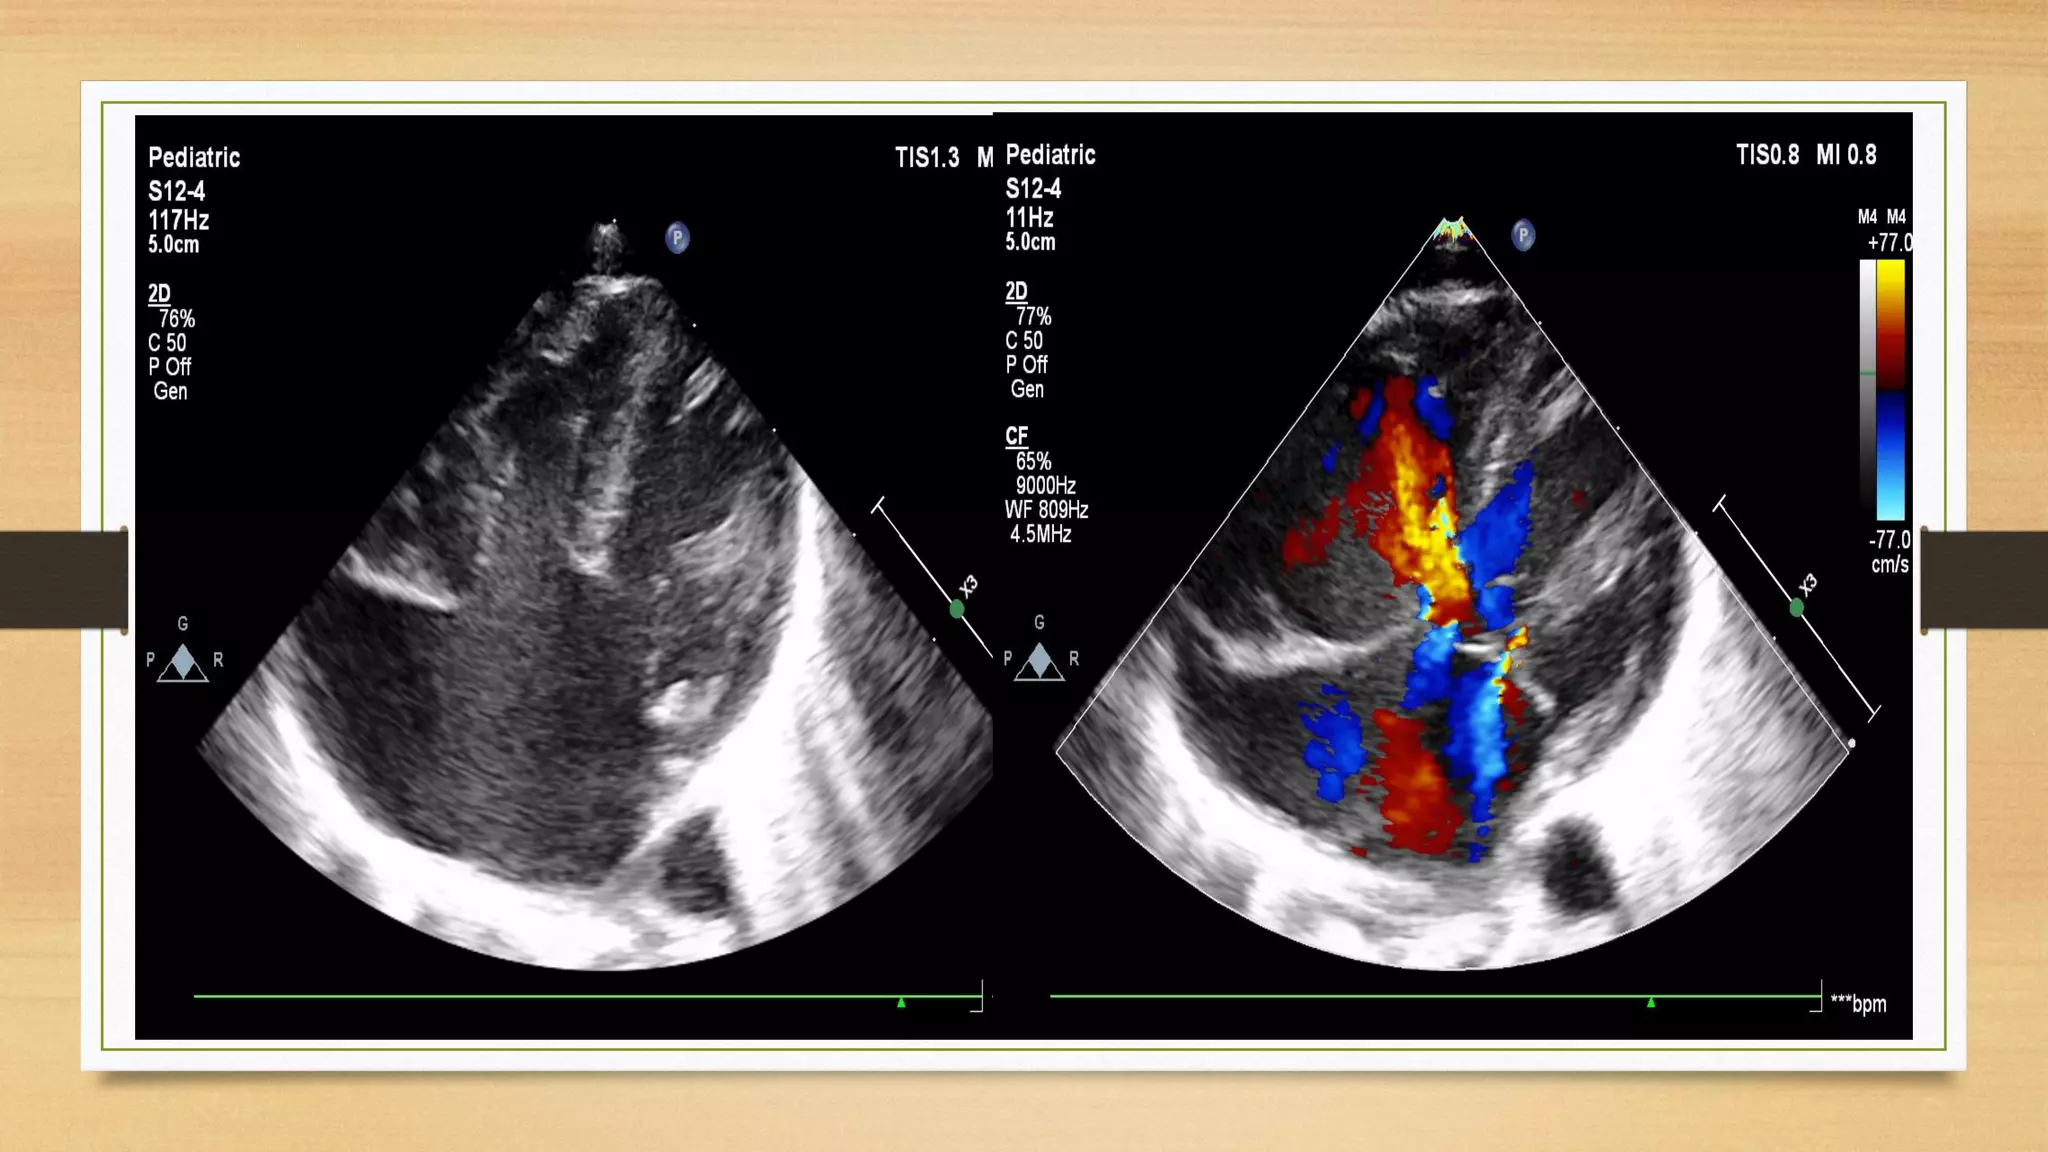

Balanced Complete A V S D

Unbalanced AVSD Complete E D